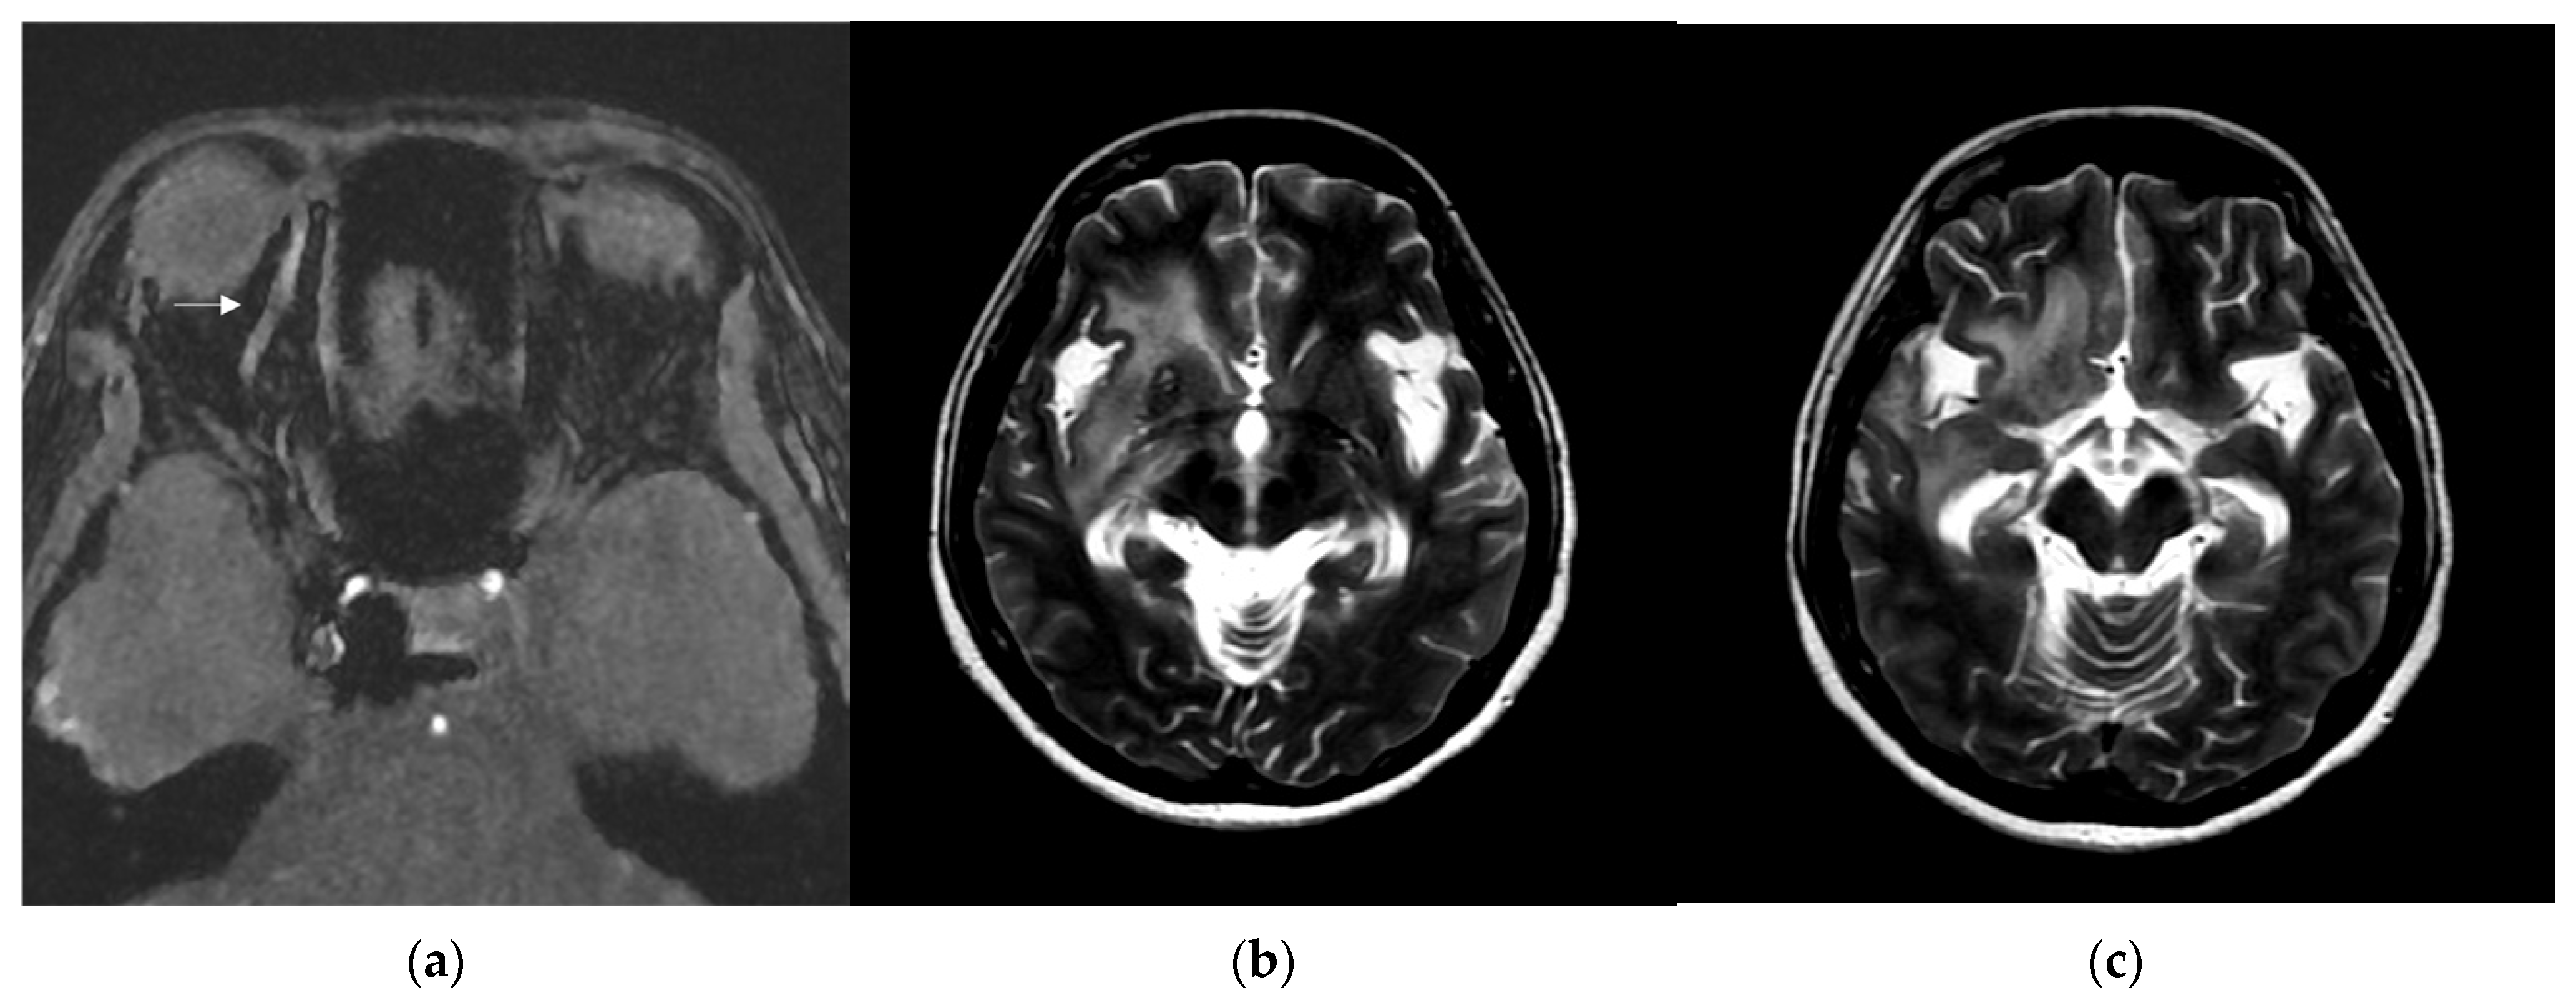

A 46-year-old woman with medically controlled hyperthyroidism was a victim of a motor vehicle accident on the road. The accident led to poor consciousness with Glasgow Coma Scale (GCS) level at E4V1M4, nasal bleeding, and left otorrhea in the patient. A brain computed tomography (CT) scan (Figure 1) showed a small subdural hematoma over the right temporal lobe, right Sylvian subarachnoid hemorrhage, and a right sellar floor fracture with sphenoid sinus hematoma upon arrival at the emergency room. The patient underwent right intracranial pressure monitor insertion for further monitoring and intensive care. Fortunately, the severity of traumatic brain injury did not progress. She gradually regained consciousness 3 days post-trauma. However, she complained of a progressive right eye floater and flash 4 weeks later, so she visited an ophthalmologist for further evaluation. Initial examination revealed right eye proptosis and conjunctival vessels engorgement, without chemosis, or tinnitus in the right ear. (Figure 2a) Rapidly progressive severe right eye exophthalmos, audible bruits, and chemosis (Figure 2b) developed within several days, highly suggesting right carotid cavernous fistula. The visual acuity and intraocular pressure data before treatment and one month post-treatment of the CCF are listed in Table 1. In addition, she became unconscious (GCS E3V2M5) and had left limb hemiplegia. A brain magnetic resonance imaging (MRI) (Figure 3a) disclosed engorgement of the right SOV and swelling of right orbital cavity (the MRI protocol we used is listed below in Table 2). In addition, high T2-weighted imaging signal changes were observed in the right corpus striatum (Figure 3b), right insular lobe, right inferior frontal lobe, right medial temporal lobe, midbrain, and pons (Figure 3c), which indicate perifocal brain edema.

Brain MRI was followed up 3 days after endovascular treatment, which disclosed significantly decreased engorgement of the right SOV (Figure 5a) and less perifocal edema in the right corpus striatum, midbrain, and pons (Figure 5b,c). Consequently, a conservative strategy was implemented to address residual CCF. We conducted a follow-up DSA one month after the TVE. The DSA revealed that the residual CCF had spontaneously resolved without additional cortical reflux (Figure 6a,b). The patient experienced a complete remission of ophthalmic symptoms (Figure 2c); her conscious level and the intraocular pressure of her right eye (Table 1) both had a favorable recovery.

Figure 3. (a) Brain magnetic resonance imaging (MRI) axial view, T1-weighted imaging with contrast disclosed engorgement of right superior ophthalmic vein (arrow head), and swelling of right orbital cavity (star); (b) brain MRI axial view, T2-weighted imaging show high T2 signal change in right corpus striatum; and (c) axial view of brain MRI T2-weighted imaging show enhancement at right insular lobe, right frontal inferior lobe, right medial temporal lobe, midbrain, and pons, which indicate perifocal cerebral edema.

Figure 5. (a) Brain MRI was followed up 3 days after endovascular treatment: axial view of brain MRI T1-weighted imaging with contrast disclosed significantly decreased engorgement of the right superior ophthalmic vein (arrow head); (b,c) brain MRI axial view, T2-weighted imaging showed less perifocal edema in the right corpus striatum, midbrain, and pons comparing to the condition before endovascular treatment.